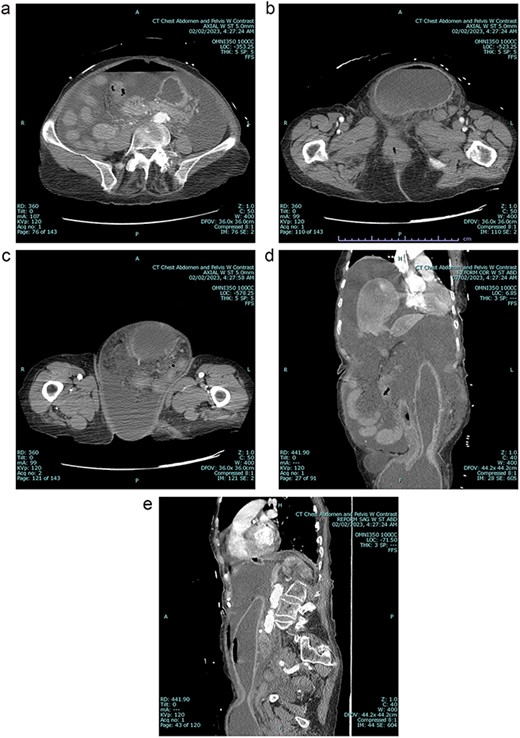

A 79 year old female patient presented to the emergency department with a two-day history of intractable nausea, vomiting, and diffuse abdominal pain. She reported having had a left groin bulge for 70 years and did not regularly see a doctor. Vital signs were notable for tachycardia and tachypnea. Physical exam was notable for a firm and distended diffusely-tender abdomen; and an associated giant incarcerated left inguinal hernia, extending down to the thigh. Laboratory evaluation revealed leukocytosis (WBC 20 K/uL), lactic acidosis (lactate 5 mmol/L), and acute kidney injury (Cr 1.5 mg/d). Computed tomography imaging demonstrated a giant left inguinal hernia containing the stomach, proximal duodenum, right hemicolon, and omentum, and associated free intraabdominal fluid and pneumoperitoneum (Fig 1). Aggressive intravenous fluid resuscitation, broad spectrum antibiotics, and vasopressor-support were started for septic shock secondary to perforated viscus. The patient was taken emergently to the OR for exploratory laparotomy. Operative findings included the following: left inguinal hernia containing the aforementioned structures, herniation of the stomach with severe gastric distension, a 0.5 cm diameter gastric perforation with surrounding necrosis at the mid portion of the lesser curve, and large volume ascites containing gastric contents. Operative interventions included the following: manual reduction of bowel and omentum from the left inguinal hernia sac, wedge resection of the perforated stomach (Figs 2 and 3), and abdominal washout. The patient was noted to have loss of abdominal domain due to the longstanding hernia. Her abdomen was closed using a biological mesh in a bridging fashion, as the fascia could not be closed primarily. Wide drainage was achieved using four 19Fr Blake drains. After surgery, the patient recovered from septic shock while being cared for in the intensive care unit. Her postoperative course was complicated by atrial fibrillation, pulmonary embolism, and COVID-19 infection. Discharge to a rehabilitation center occurred on hospital day 20. Follow up computed tomography imaging is as shown (Fig 4). Staged repair of the left inguinal hernia with permanent prosthetic mesh is planned in the near future.

A Preoperative axial view at level of mid abdomen, demonstrating free intraabdominal fluid and air 1b: Preoperative axial view at level of groin, demonstrating stomach-containing left inguinal hernia 1c: Preoperative axial view at level of the mid thigh, demonstrating left inguinal hernia containing both the stomach and other viscera 1d: Preoperative coronal view, demonstrating stomach being pulled down into inguinal hernia sac 1e: Preoperative sagittal view, demonstrating stomach being pulled down into inguinal hernia sac, and associated free intraabdominal air.